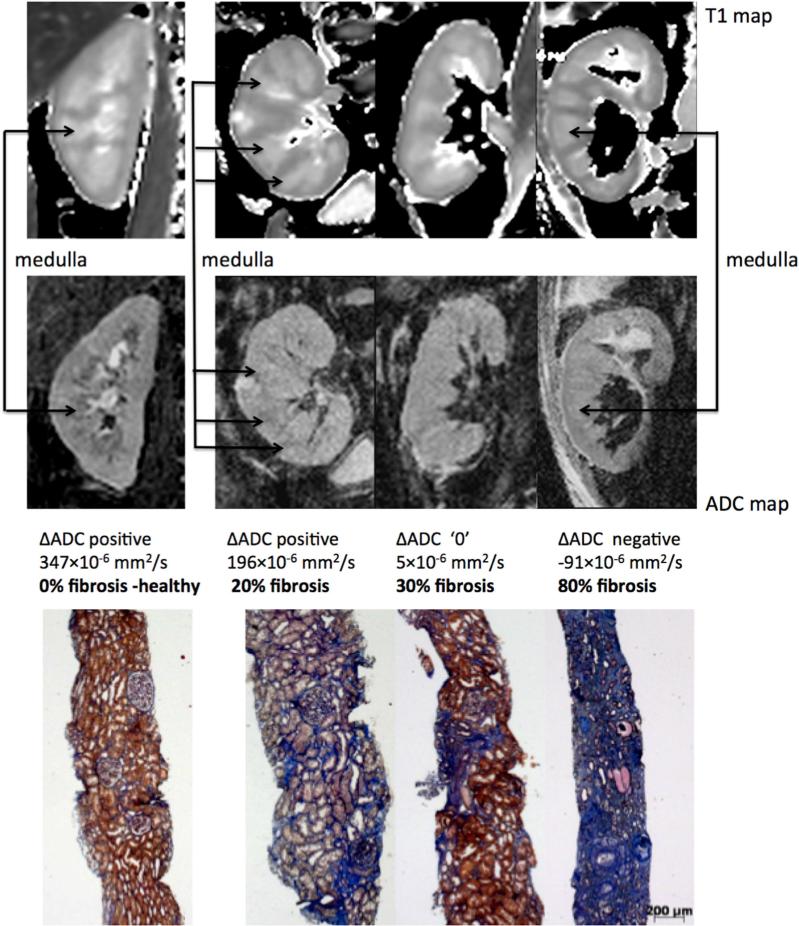

The relationships between the heart and the kidney occupy an important place in the clinic, but are still poorly understood at the fundamental level. For example, the majority of patients with heart failure die of heart-related, not kidney-related problems. The goal of this project is to use MRI to correlate different renal and cardiac parameters in patients, particularly those related to tissue fibrosis. As part of an FNS project, we have developed a RESOLVE-based protocol that allows us to significantly improve image quality and resolution, to robustly measure diffusion parameters in the renal medulla and cortex. In collaboration with the Department of Nephrology, we conducted a study of 130 patients with chronic kidney disease and we were able to show a significant correlation between the cortico-medullary difference of the diffusion coefficient measured by MRI and the level of fibrosis measured by biopsy. In order to extend the validity of these results, we will start a multicenter study as part of a European COST project. We are also working on an MRI protocol to simultaneously measure cardiac and renal function in a clinically acceptable time.